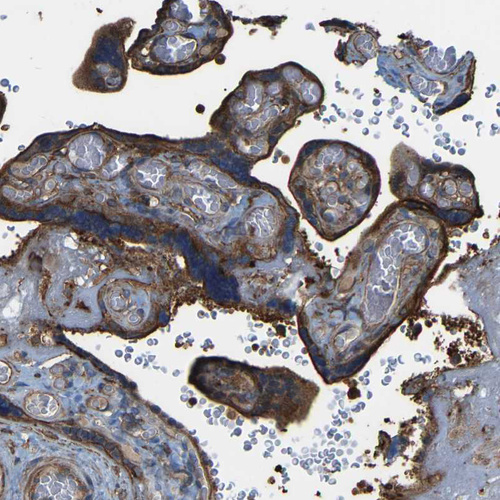

Immunohistochemical staining of human lymph node, placenta, stomach and testis using Anti-SAMD9L antibody HPA019465 (A) shows similar protein distribution across tissues to independent antibody HPA019461 (B).